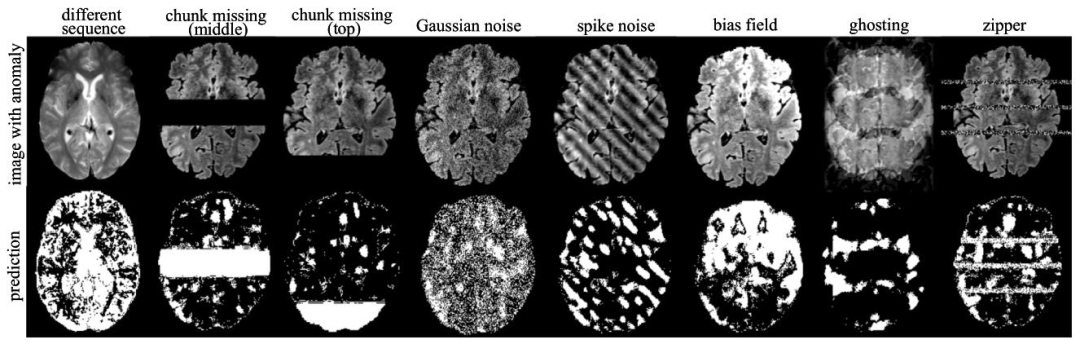

5.1. Synthetic artifact detection on 3D images

We first evaluate performance of our model for detecting artifactsthat may appear as unexpected anomalies during deployment. Methods for detecting unexpected artifacts during acquisition are usefulfor implementing quality-assurance frameworks. It is often difficult toannotate precise ground truth segmentation labels for artifacts, particularly when they manifest as global patterns across the entire image.Additionally, image-level detection is typically sufficient for identifyingsuch anomalies. Therefore we evaluate performance based on artifactdetection rather than segmentation.We begin by testing the model’s ability to detect synthetic artifacts.We train models on cognitively normal data from ADNI using the FLAIRsequence, which contain no pathology or artifacts. This defines the indistribution normal data. To evaluate anomaly detection, we first assessthe model’s ability to detect scans of a different sequence. Then, wesimulate various types of anomalies (anomalies closer to the trainingdistribution) in reference of Graham et al. (2023) and Ravi et al. (2024)by generating images with missing chunks in the middle or top regionsof the brain, adding Gaussian noise, adding spike noise, bias field,random ghosting, or zipper artifact as illustrated in Fig. 5 first row. Thesimulated anomalies are added to FLAIR from the ADNI validation set,while the original, unaltered images are used as in-distribution normalcontrol samples for performance evaluation. A detailed description ofeach artifact is provided below.

5.1 3D图像上的合成伪影检测 我们首先评估所提模型在检测部署过程中可能出现的意外伪影(表现为异常)方面的性能。在图像采集阶段检测意外伪影的方法,对构建质量保障框架具有重要意义。然而,为伪影标注精确的分割真值标签往往存在难度,尤其是当伪影在整幅图像中呈现全局分布模式时。此外,对于此类异常的识别,通常只需实现图像级别的检测即可。因此,我们基于伪影检测(而非分割)来评估模型性能。 我们首先测试模型检测合成伪影的能力。模型的训练数据来自ADNI数据集(FLAIR序列)中认知功能正常被试的图像,这些图像不含任何病症或伪影,构成了“分布内正常数据”。为评估异常检测效果,我们首先测试模型对不同序列扫描图像的检测能力。随后,参考Graham等人(2023)和Ravi等人(2024)的研究,我们模拟了多种类型的异常(与训练分布更接近的异常):生成脑部中间或顶部区域存在“缺失块”的图像、添加高斯噪声的图像、添加尖峰噪声的图像,以及存在偏置场、随机重影或拉链伪影的图像(如图5第一行所示)。这些模拟异常被添加到ADNI验证集的FLAIR序列图像中,而未经修改的原始图像则作为“分布内正常对照样本”,用于性能评估。各类伪影的详细说明如下。

Fig. 5. Visualization of anomaly detection results on images with synthetic anomalies using our method 𝐼 𝑡𝑒𝑟𝑀𝑎𝑠𝑘3𝐷. The first row shows the input images withsimulated anomalies, while the second row displays the corresponding detected anomaly areas.

图5 采用所提方法IterMask3D对含合成异常图像的异常检测结果可视化 第一行展示含模拟异常的输入图像,第二行展示对应的检测到的异常区域。